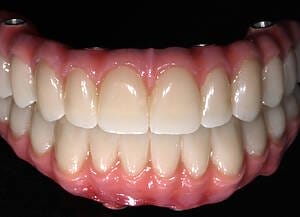

The moment Natalie saw her new smile, the emotion was undeniable. What had once been a source of discomfort, anxiety, and embarrassment had been completely transformed. Her new teeth restored full function and aesthetics, giving her back the ability to eat, speak, and smile without hesitation.

This result was more than cosmetic. It marked the end of a long journey filled with fear and hesitation, and the beginning of a new chapter defined by confidence and well-being. Natalie’s story is a powerful example of how modern dentistry, when led by skilled professionals and supported by cutting-edge technology, can restore much more than teeth.

My first look in the mirror with my new set of teeth was incredible. I’m in disbelief and I feel a bit overwhelmed because it looks so good. At the same time, it looks so natural, it is the shape of my natural teeth and smile. They feel comfortable, I can speak with them. I feel very confident that this will work very well for me.